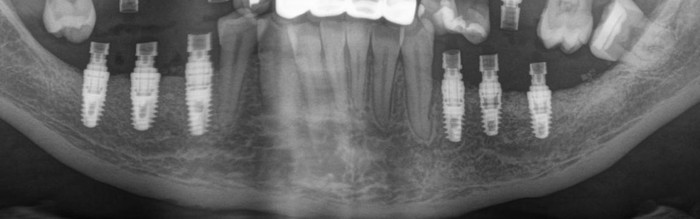

Дабы не перегружать вас обилием одинаковых картинок, я оставлю один рентгеновский снимок, но отмечу, что установка имплантатов на верхней и нижней челюсти проводилась с разницей в 10 дней.

На верхней челюсти было дополнительно удалено два боковых резца с одномоментной установкой имплантатов, так же они были установлены в области четверок и шестых зубов. Дополнительно было проведено наращивание костной ткани - двусторонний синус - лифтинг. О том, что это такое, можно почитать ТУТ и ТУТ.

Контрольный рентгеновский снимок: